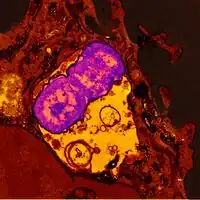

-

Gram stained smear of sputum for observation -

Ultrastructural morphology of Klebsiella pneumoniae- 1-6) Six different photomicrographic preparations